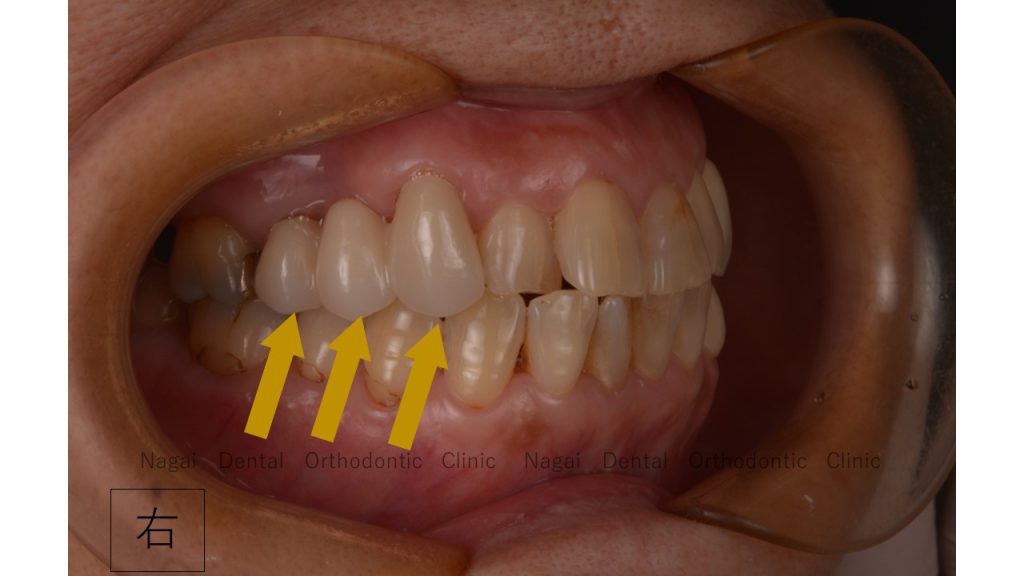

Bさんの歯列は向きがおかしく、奥歯以外は噛めていません。

Bさんは奥歯6番・7番でしか噛めていないので、

●右上3番・4番・5番の噛み合わせを調整するため、ぐらぐらの4番を抜き3番から5番のブリッジ

左右共に、3番から5番にもしっかりとした噛み合わせを作ることを考えました。